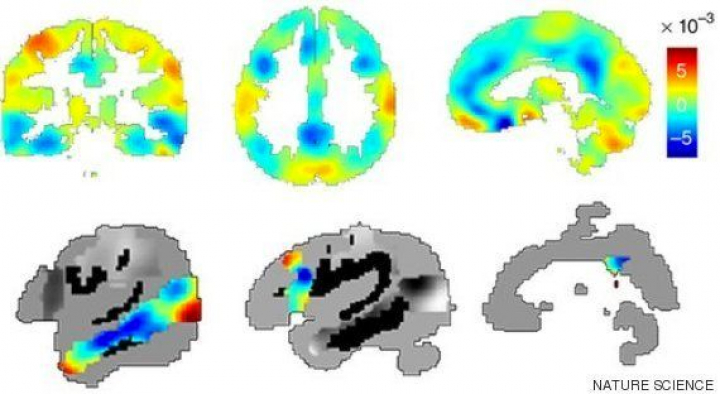

Mediante el análisis de imágenes de resonancia magnética, los científicos han observado cómo en las mujeres que han vivido su primer embarazo se reduce el volumen de la materia gris en regiones implicadas en las relaciones sociales.

La investigación mostró una reducción simétrica en el volumen de la sustancia gris en la línea media cortical anterior y posterior, así como en secciones específicas de la corteza prefrontal y temporal en las mujeres embarazadas.

Estas zonas forman un mapa que coincide, en gran medida, con una red que los neurocientíficos asocian con los procesos implicados en las relaciones sociales.